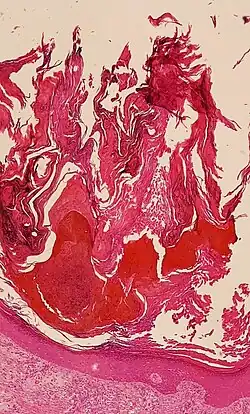

![]() Histologic image of human epidermis in thick skin | |

The stratum corneum (Latin for 'horned/horny layer') is the outermost layer of the epidermis of the skin. Consisting of dead tissue, it protects underlying tissue from infection, dehydration, chemicals, and mechanical stress. It is composed of 15 to 20 layers of flattened cells with no nuclei or cell organelles.

The human stratum corneum comprises several levels of flattened corneocytes that are divided into two layers: the stratum disjunctum and stratum compactum. The stratum disjunctum is the uppermost and loosest layer of skin. The skin's protective acid mantle and lipid barrier sit on top of the stratum disjunctum.[5] The stratum compactum is the comparatively deeper, more compacted and more cohesive part of the stratum corneum.[6] The corneocytes of the stratum disjunctum are larger, more rigid and more hydrophobic than those of the stratum compactum.[7]

The thickness of the stratum corneum varies throughout the body. In the palms of the hands and the soles of the feet (sometimes knees, elbows,[9] and knuckles) this layer is stabilized and built by the stratum lucidum (clear phase) which allows the cells to concentrate keratin and toughen them before they rise into a typically thicker, more cohesive stratum corneum. The mechanical stress of heavy structural strain causes this stratum lucidum phase in these regions which require additional protection in order to grasp objects, resist abrasion or impact, and avoid injury. In general, the stratum corneum contains 15 to 20 layers of corneocytes. The stratum corneum has a thickness of between 10 and 40 μm.